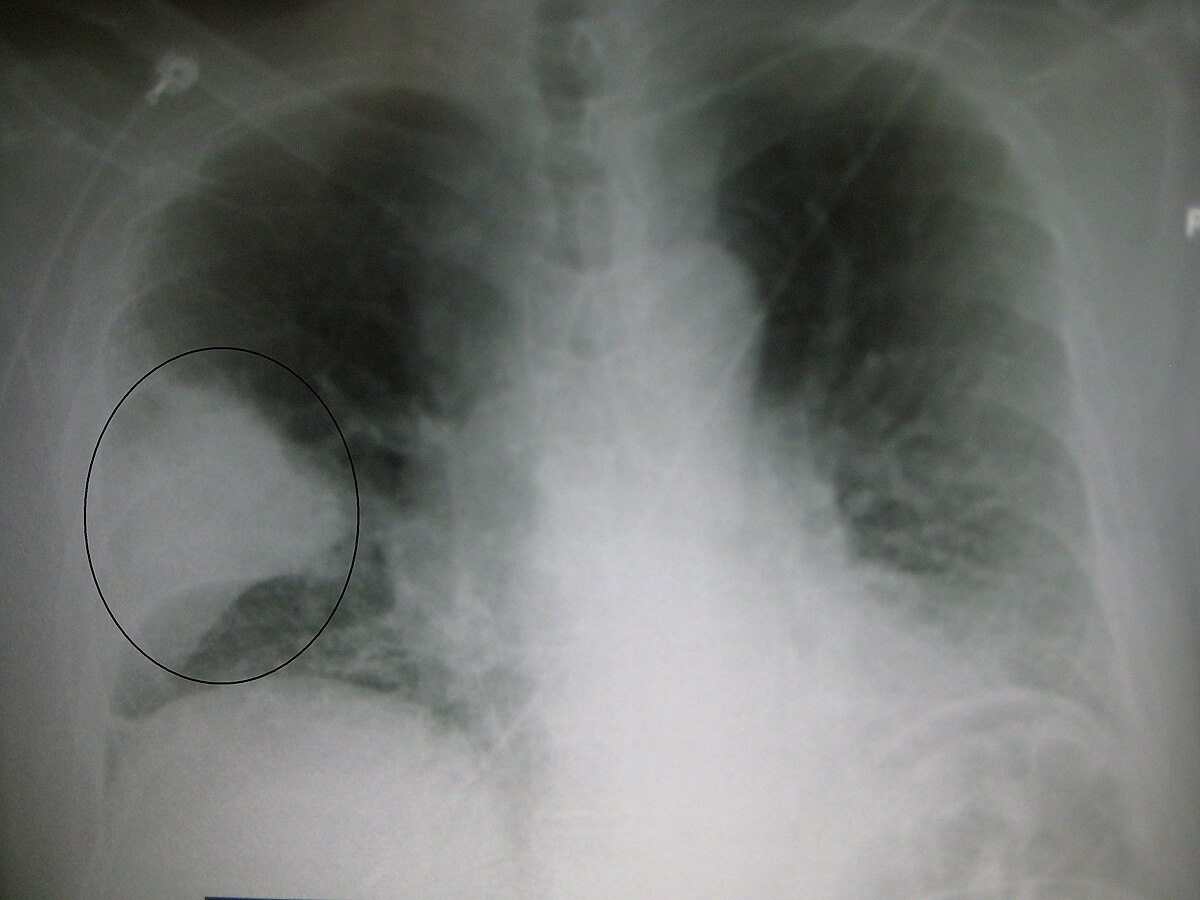

12 ноября — Всемирный день борьбы с пневмонией. Статистика